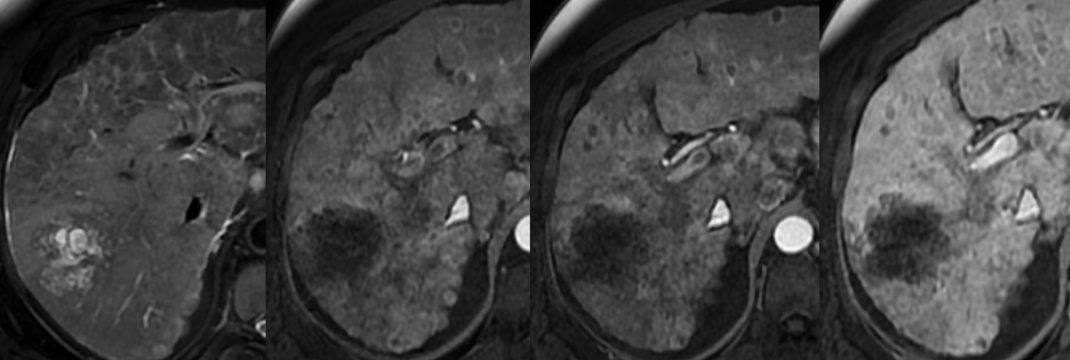

IRM

- T1 FS: Plus hypo que le parenchyme pancréatqiue

- T2 Hyper-périphérique (viable) et hypo- central (fibrose)

- T1 gd1+ : Meilleure détection des petits CholangioK que le CT